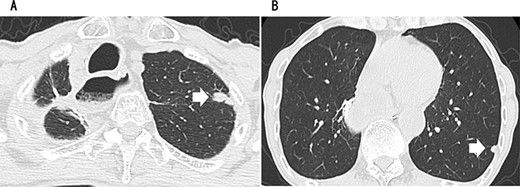

A 79-year-old man underwent right subthoracic esophagectomy and posterior mediastinal reconstruction for esophageal cancer (squamous cell carcinoma, pT3N4M0 Stage IVa) 9 years ago. The patient had previously undergone four cycles of CDDP+5-FU. After esophagectomy, the patient developed ileus three times; it was conservatively managed. During the third hospitalization, chest computed tomography (CT) showed a circular nodule measuring 1.4 cm in the S1 apex of the right upper lobe and a nodule measuring 0.9 cm outside S2 (Fig. 1). No findings were suggestive of esophageal cancer recurrence. 18F-Fluorodeoxyglucose-positron emission tomography revealed FDG uptake increated in the nodule in the right lung S1 with a maximum standardized uptake value of 4.3 and in the nodule in the right lung S2 with a maximum standardized uptake value of 2.7. No significant hilar or mediastinal lymph node swelling or distant metastases were detected. Bronchoscopic biopsy did not reveal any signs of malignancy. Based on the above findings, we suspected multiple lung metastases secondary to esophageal cancer, metachronous primary lung cancer or intrapulmonary metastasis secondary to primary lung cancer. We performed partial resection of the two nodule in the upper lobe of the right lung for diagnosis and treatment. Histopathological examination revealed squamous cell carcinoma (Fig. 2). Immunostaining was performed to determine whether the primary organ was the esophagus or the lung, but no diagnosis was made. On request, no additional chemotherapy was administered. Chest CT after 1 year and 2 months of right lung resection revealed a nodule measuring 1.5 cm at the apex of the left lung and a nodule measuring 0.9 cm below the S9 pleura of the left lung (Fig. 3).

CT showing a circular nodule measuring 1.4 cm in the S1 apex of the right upper lobe (A) and a nodule measuring 0.9 cm outside S2 (B).